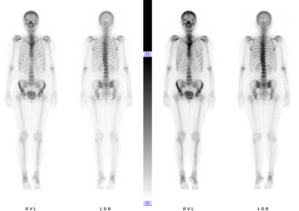

Skelettszintigraphie

Ca. 2 bis 3 Stunden nach der Injektion einer radioaktiv markierten Substanz werden die Bilder mit der Gammakamera aufgenommen. Während der Wartezeit sollten Sie ausreichend trinken (etwa 0,5-1 Liter) und die Blase entleeren. Die Bildaufnahme im Anschluss dauert ca. 30 min, evtl. länger, wenn Einzelaufnahmen von bestimmten Körperteilen notwendig sind. Evtl. erfolgen zusätzliche Bildaufnahme mit niedrigdosierter CT, um die genaue Aussage über die Lokalisation von Krankheitsherden zu ermöglichen. Bei bestimmten Fragestellungen, häufig zur Abklärung von Entzündung, läuft die Untersuchung in mehreren Phasen ab. In diesem Fall werden die ersten Bildaufnahmen unmittelbar nach der Injektion von radioaktiver Substanz sowie erneut ca. 2 Stunden später durchgeführt.